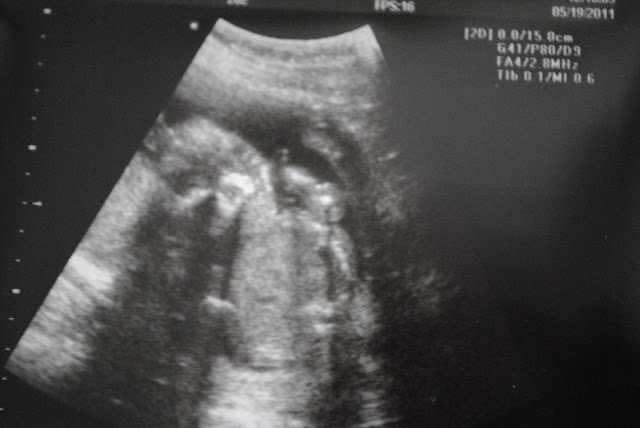

I had to get some blood work done and Dr. Dameron told me I had low progesterone. The stuff that helps the placenta grow and attach to the uterus and support the baby. I had to make medicine for that which made me super sick. The plus side of it though was I had to go in every 2 weeks for an ultrasound! :)

| Little peanut. Only 6 weeks new! |

| 8 weeks |

| 10 weeks! I look like a little person |

| 20 weeks. I didn't want to cooperate so mom and dad could find out if I am a little boy or girl! |

| 21 weeks sucking my thumb |

| I'M A BOY!! |